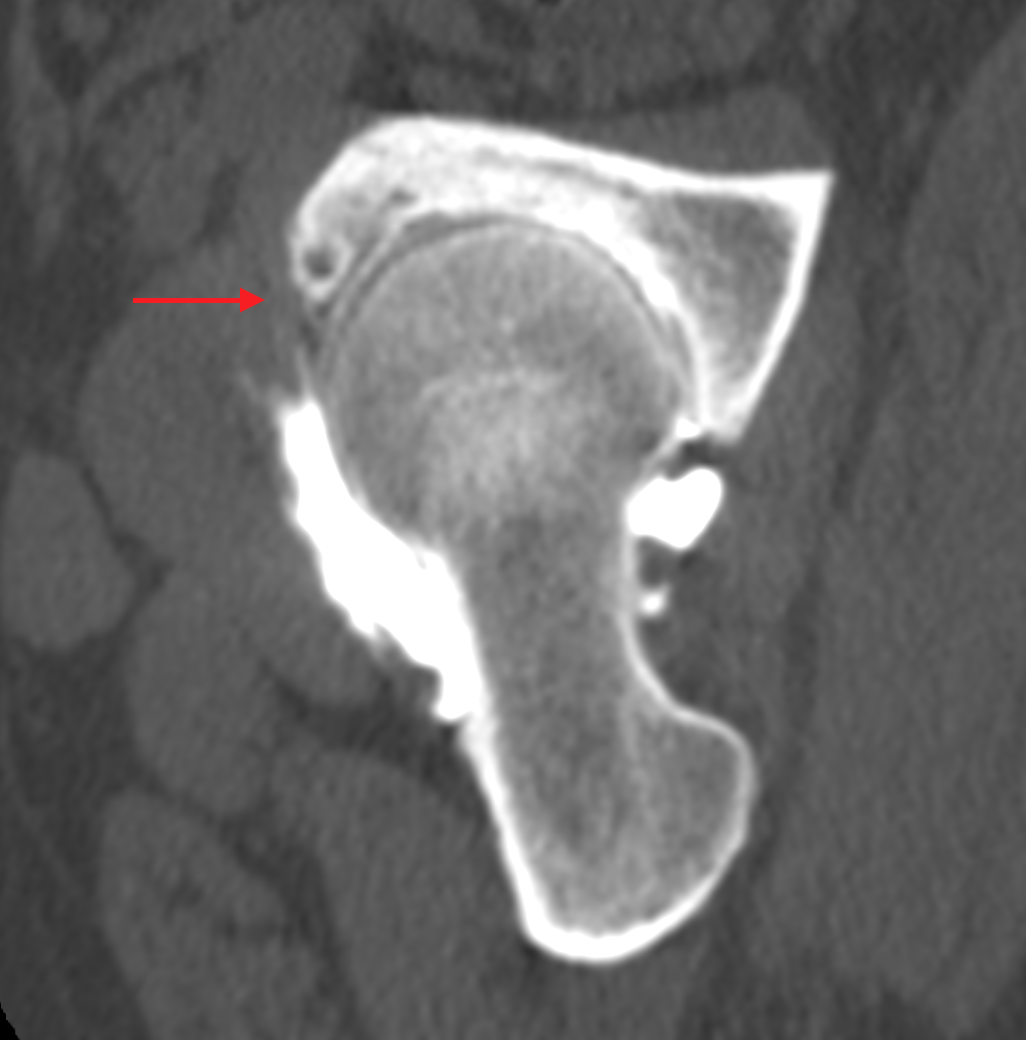

Złamanie zmęczeniowe panewki stawu biodrowego

Stress fracture of the acetabulum

Surgery

Nowak P., Maczuch J., Skupiński J.

Pelvic fatigue fractures most often involve the sacrum and hip bones. Their cause is repetitive micro-injuries to which people who engage in regular sustained physical activity are exposed. One of the rarest locations of a fatigue fracture is the acetabulum of the hip joint.